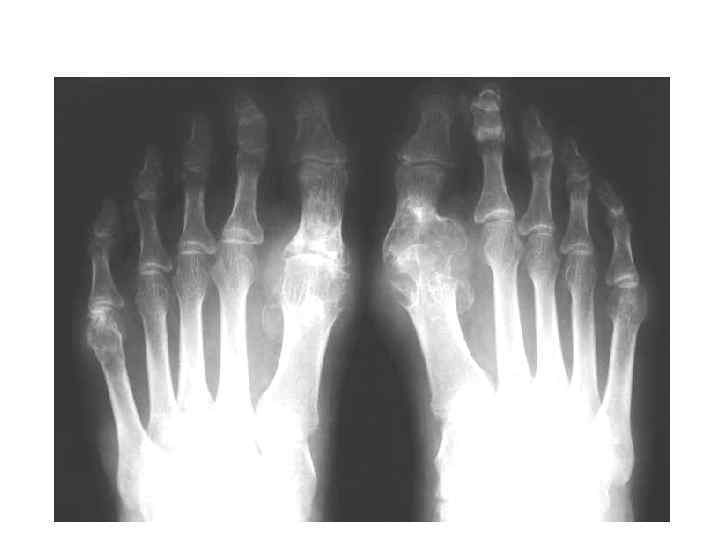

МРТ диагностика подагрического артрита: изображения и результаты исследований